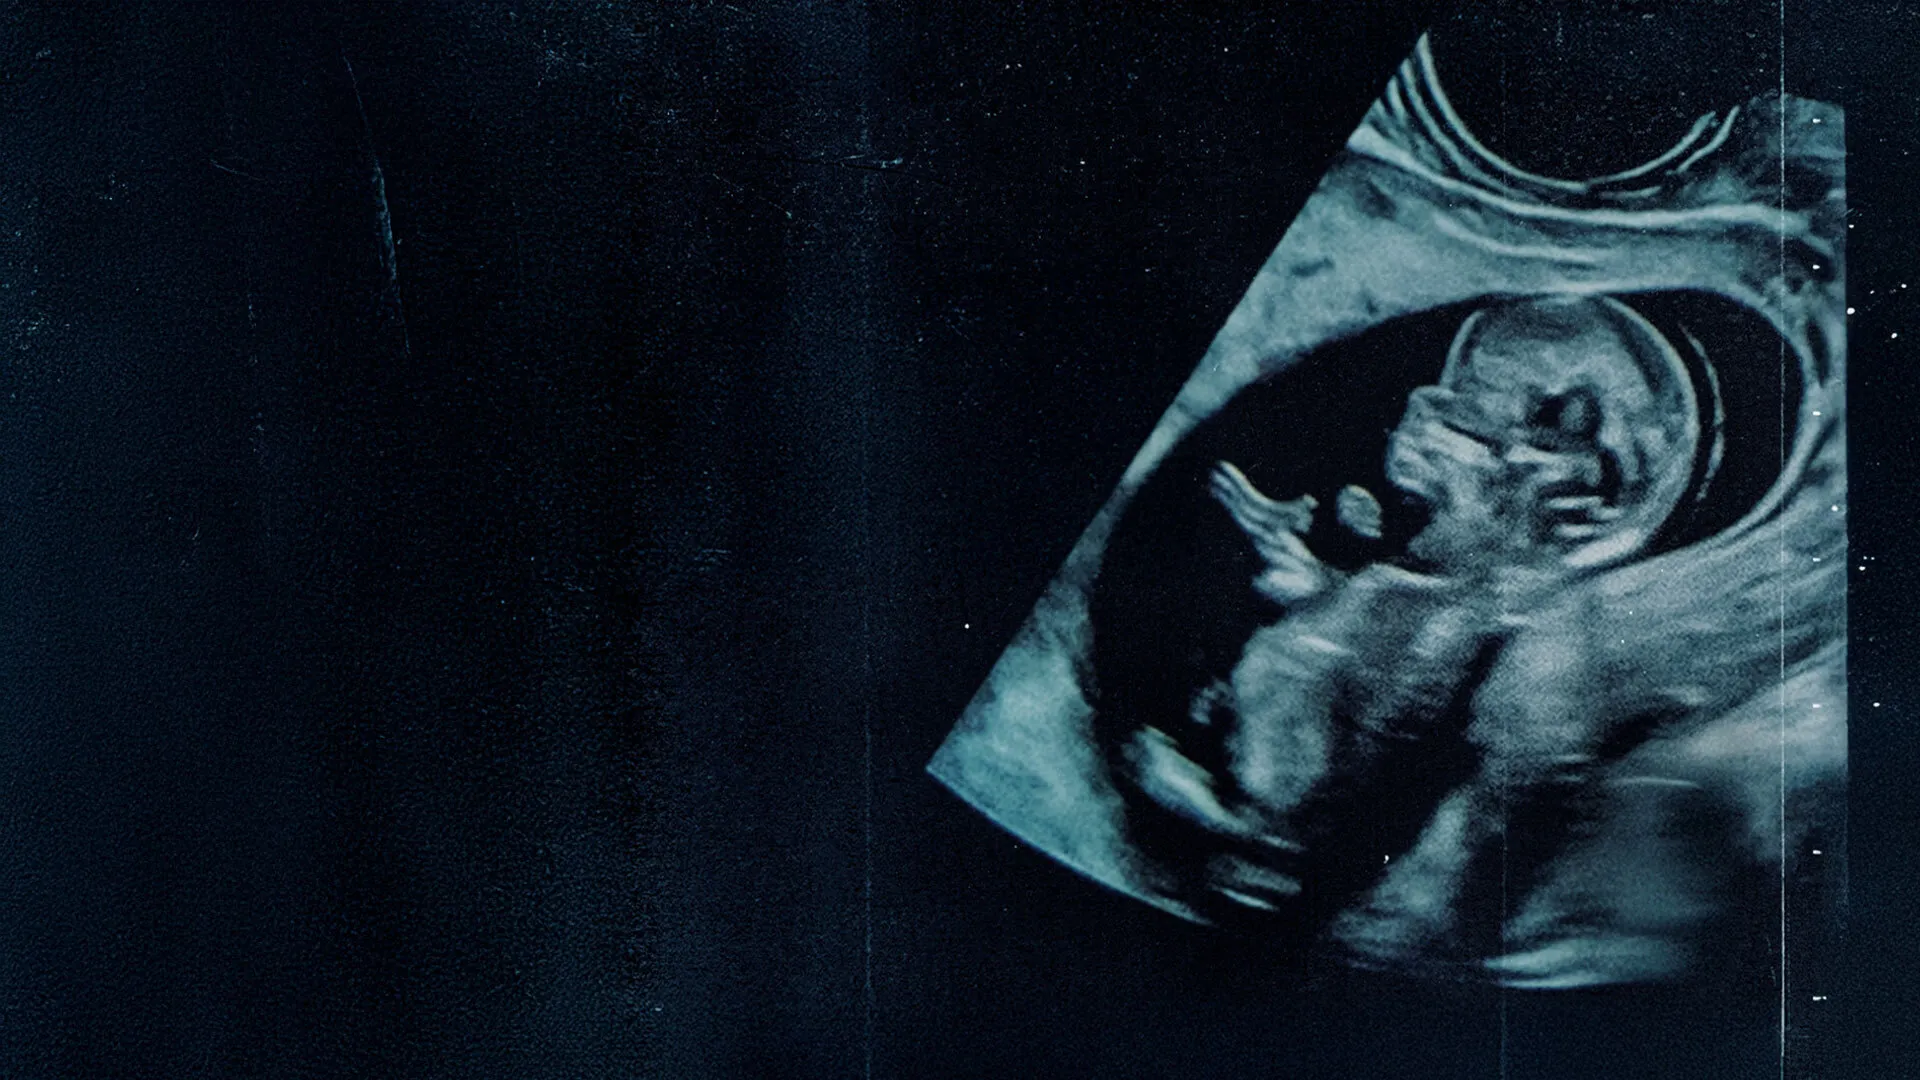

Sinopse: Você já parou para pensar no valor inestimável da vida, diante da escolha mais desafiadora e fascinante da existência? Nosso documentário o convida a confrontar o dilema central da nossa humanidade: como podemos apoiar as mães a fazerem a escolha pela vida e reconhecer a dignidade inegável do ser que ainda pode nascer? É hora de entender por que ser humano vale a pena. Curiosidades: O documentário apresenta uma visão abrangente do debate, ouvindo diversas perspectivas; A série busca entender por que devemos apoiar as mães que se sentem pressionadas e em dúvida; Dirigido por Elton Mesquita. Assista agora: Disponível para assinantes Brasil Paralelo. Experimente e assista hoje mesmo.